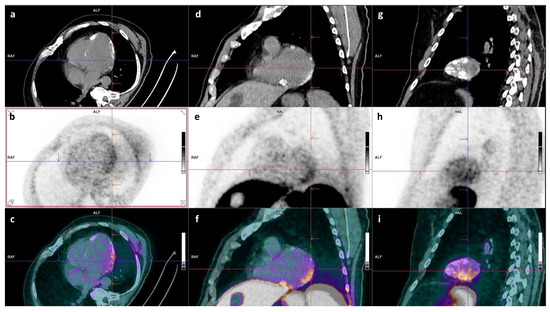

Figure 2. Example of calcifying myocarditis under Revlimid on [68Ga]-GaDOTATOC PET/CT ((ac): short-axis slices, (di): long-axis slices). A 66-year-old patient showing increased left myocardial uptake, particularly in the infero-latero-basal region, adjacent to subepicardial calcifications (myocardial/blood SUVmax ratio of 2.75). CMR was inconclusive due to the extent of calcifications.

A recent retrospective study of 511 oncological [68Ga]Ga-DOTATOC PET/CT showed significant myocardial uptake in 26.9% [61]. Among them, 31 patients were recruited at the time of acute myocarditis diagnosis. An increased uptake was consistently seen on at least two contiguous left ventricle segments, associated with a marked decrease in blood activity, and with myocardial uptake predominantly localizing to inferior and inferior-lateral segments. The myocardial/blood SUVmax ratio threshold of 2.2 yielded a sensitivity of 87% and specificity of 77.4% for the diagnosis of acute myocarditis compared to the less intense and less extensive uptake described in the other patients. Adding the uptake volume could enhance the diagnostic performance rates. These preliminary findings suggest that SSTR PET/CT could be an additional tool to CMR when the diagnosis of myocarditis is challenging (Figure 2).